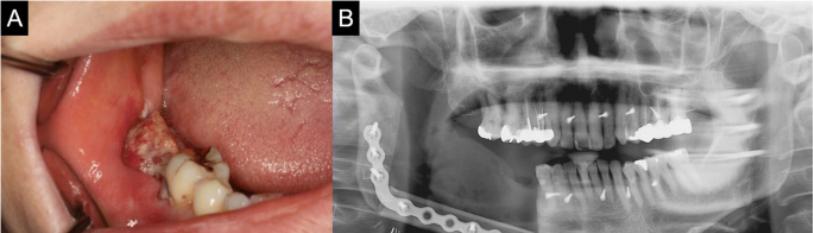

Figure 4A: Young female patient of 17 years of age with extensive Rhabdo—myosarcoma of the left side of the mandible.

Figure 4B: Lateral oblique of left lower jaw showing sever destruction and osteolytic changes.